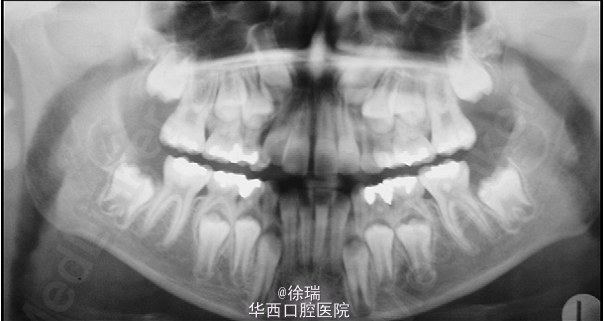

尖牙的异位萌出多见于上颌,可造成相邻牙齿的根尖吸收。最近遇到了一个病例,15岁的女孩儿,安氏III类,上颌尖牙阻生,因为尖牙的位置太过靠近侧切牙和中切牙根方,邻牙发生了严重的根尖吸收。那这样的病情又该如何矫正呢?